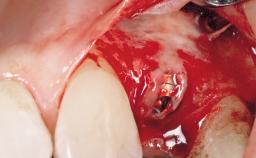

Late Flapless Placement of an Implant in a Maxillary Left Central Incisor Site

A 39-year-old male patient presented with a chief complaint of discomfort and gingival discoloration around his maxillary left central incisor. He was in good general health and was a non-smoker. His past dental history was significant because of the traumatic fracture of tooth 21 in a sporting accident at age 13. Initial dental treatment included endodontic therapy and a full-coverage restoration. The patient became symptomatic 5 years later, when structural failure of the tooth resulted in the dislodgment of the crown. Endodontic retreatment, apical surgery, and post-and-core restoration were performed.